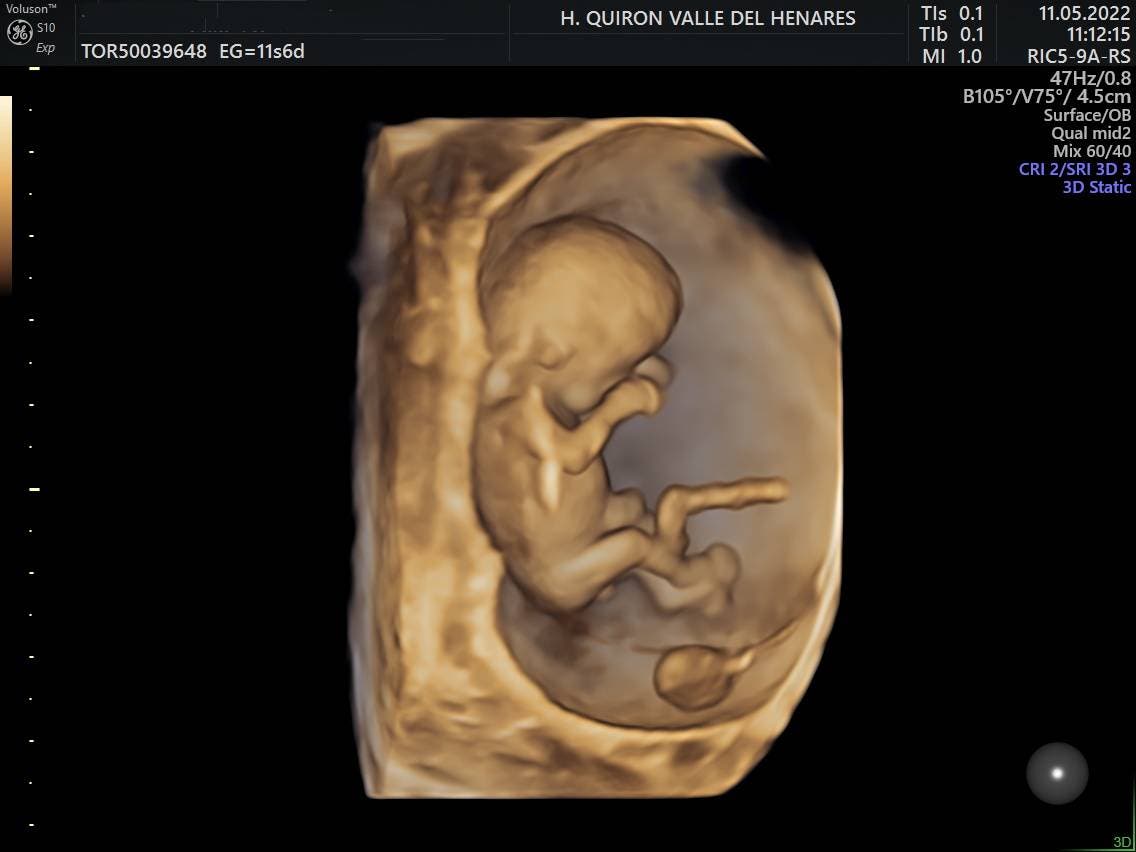

El Hospital Quirónsalud Valle del Henares incorpora un nuevo ecógrafo con tecnología 5D

El Hospital Quirónsalud Valle del Henares, en Torrejón de Ardoz, ofrece la posibilidad de realizar ecografías gestacionales 5D. Este tipo de exploración permite obtener una imagen muy realista del bebé y se puede realizar en cualquier etapa de la gestación -aunque lo recomendado es realizarla entre las semanas 28 y 32 de gestación, ya que técnicamente es el mejor momento y es mucho más probable obtener imágenes de buena calidad-.

«Realizar esta ecografía con nuestro equipo de diagnóstico prenatal tiene un valor añadido», señala la Dra. Rocío Vellido Cotelo, Jefa Asociada de Ginecología y Obstetricia del Hospital Quirónsalud Valle del Henares, «dado que quien realiza la prueba es un especialista en la materia, siempre se completa la exploración con un examen morfológico y de perfil biofísico fetal, que permita valorar el estado de bienestar del bebé más allá de la captura de vídeos y fotografías».